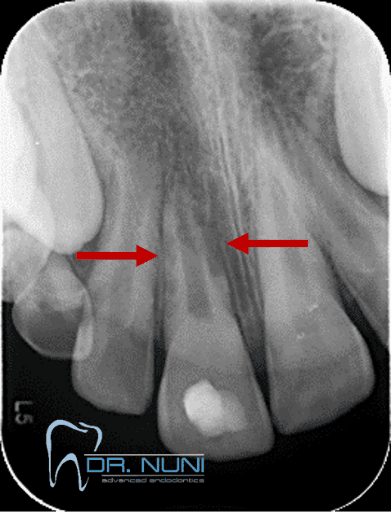

הנזקים הנגרמים כתוצאה מאנקילוזה בגיל צעיר (החץ מסמן את השן האנקילוטית)

לפני דקורונציה